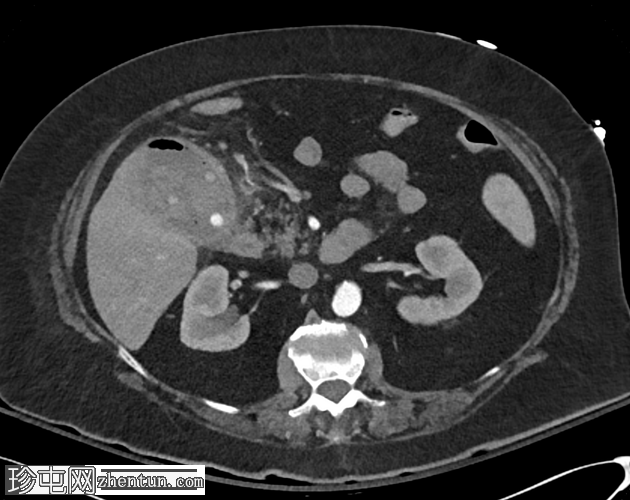

5.png

正面

腹腔干

血管造影证实存在胆囊动脉假性动脉瘤,并伴有活动性出血征象。

行胆囊动脉栓塞术,术后血管造影显示疗效满意。

CT影像学表现符合出血性胆囊炎合并胆囊十二指肠瘘,导致呕血。此外,还可见胆囊动脉假性动脉瘤,并伴有活动性出血征象。

行血管造影引导下栓塞术,患者病情迅速好转,消化道出血停止,临床状况改善。